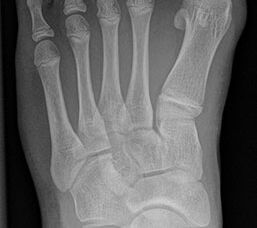

Standard ist die belastete Röntgenaufnahme des Fußes dorso-plantar und seitlich. Günstig ist eine Röhrenkippung von 10°-20°, um die Gelenke der Lisfranc-Linie einsehen zu können.

Ergänzend kann eine Schrägaufnahme hilfreich sein. Bei Metatarsalgien oder Pathologien der Sesambeine liefert die Sprinteraufnahme zusätzliche Informationen. Bei einer Pes planovalgus Fehlstellung wird ergänzend ein Saltzman view durchgeführt.

• Hallux valgus Winkel

• Hallux valgus interphalangeus Winkel

• Intermetatarsalwinkel I zu II

• Distaler Metatarsale Gelenkwinkel (PASA)

• Form des Mittelfußknochenkopfes

• Winkel Metatarsale I Basis zum Os cuneiforme mediale

• Metatarsalindex

• Elevation/ Plantarisierung I. Strahl

• Pes metatarsus adductus

• Wachstumsfugen

• Coalitiones

• Akzessorische Knochen